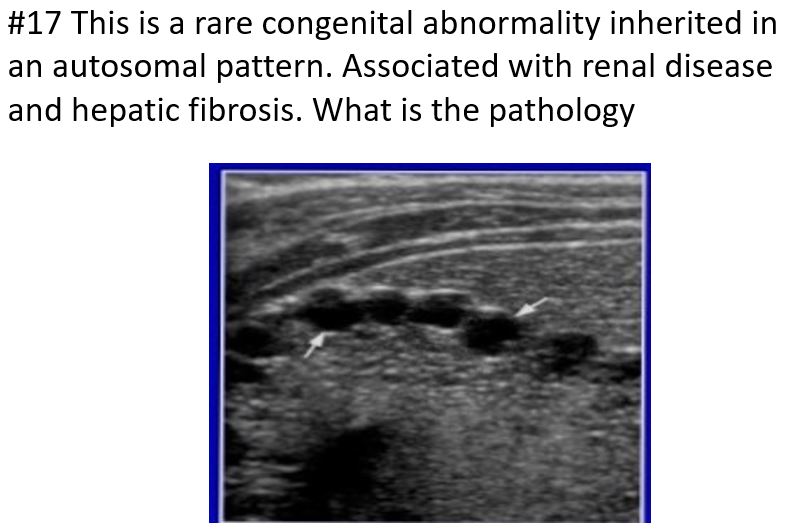

Rare congenital abnormality most likely inherited in an autosomal recessive fashion.

Communicating cavernous ectasia of the intrahepatic ducts characterized by congenital segmental saccular cystic dilation of major intrahepatic bile ducts.

Found in the young adult or pediatric population;

may be associated with renal disease or congenital hepatic fibrosis

symptoms

Recurrent cramplike upper abdominal pain, secondary to biliary stasis, ductal stones, cholangitis, and hepatic fibrosis.

Two types of Caroli’s disease

Simple classic form

More common form associated with periportal hepatic fibrosis

Caroli’s Disease (medullary sponge kidney) is strongly associated

what is this disease associated with…this is carolis disease

MEDULLARY SPONGE KIDNEY